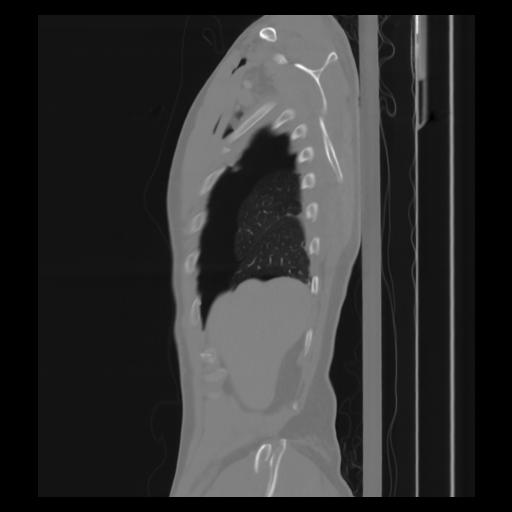

30 CUERPO,CE,Sagittal,3.000,CUERPO,Sagittal,